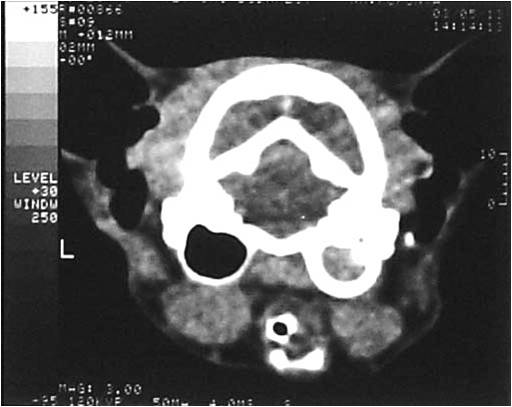

A koponyán belüli vérzések és a koponya traumás sérülései (4. ábra) is jól kimutathatóak. Hasonlóan fontos szerepe van a közép-, és belsőfül betegségeinek megállapításában, mert biztosan felismerhető a

dobüregnek, vagyis a középfülnek a megbetegedése (5. ábra). Az agyvelő és a fül vizsgálata mellett a gerinc vizsgálatában is nagy szerepet játszik, mert a hagyományos röntgenvizsgálattal látott elváltozásokról